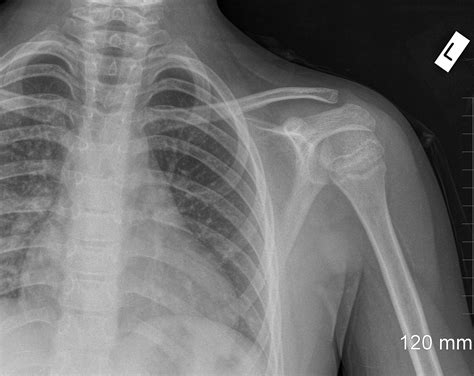

Understanding the significance of a shoulder X-ray normal result is crucial for both medical professionals and patients. A shoulder X-ray is a common diagnostic tool used to evaluate the bones, joints, and surrounding soft tissues of the shoulder. This imaging technique helps identify fractures, dislocations, arthritis, and other abnormalities. However, interpreting a shoulder X-ray normal result requires a thorough understanding of the anatomy and potential pathologies that can affect the shoulder.

A shoulder X-ray is a non-invasive imaging test that uses electromagnetic radiation to produce images of the shoulder joint and surrounding structures. This test is often the first step in diagnosing shoulder pain or injury. The X-ray can reveal fractures, dislocations, arthritis, and other bone abnormalities. However, it may not always show soft tissue injuries, such as tears in the rotator cuff or ligaments.

When a shoulder X-ray normal result is reported, it means that the X-ray images do not show any visible abnormalities in the bones or joints. This can be reassuring for patients experiencing shoulder pain, as it indicates that there are no obvious fractures or dislocations. However, it is important to note that a normal X-ray does not rule out all possible causes of shoulder pain.

Shoulder injuries can significantly impact daily activities and quality of life. Understanding the significance of a shoulder X-ray normal result and the potential causes of shoulder pain is crucial for effective diagnosis and treatment. While a normal X-ray indicates that there are no visible bone abnormalities, it does not rule out all possible causes of shoulder pain. Additional diagnostic tests, such as MRI or ultrasound, may be necessary to identify the underlying cause of shoulder pain and develop an appropriate treatment plan.